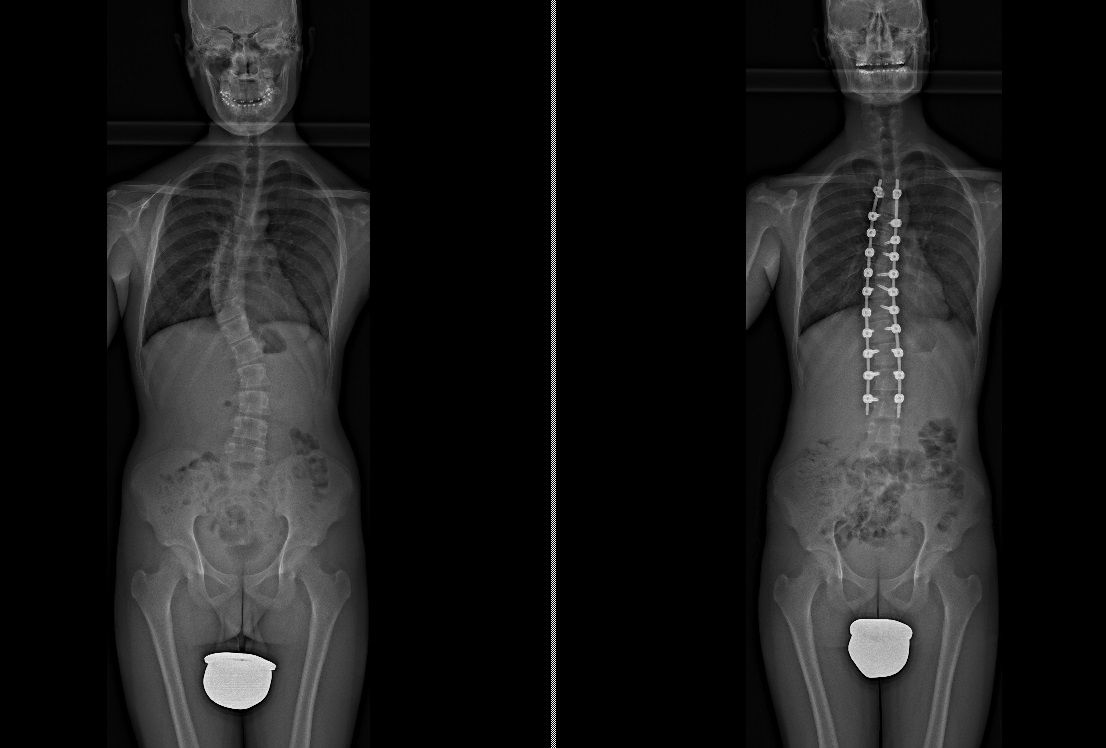

Foto e video